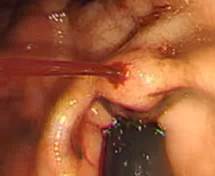

4. 정맥류를 동반한 간암

간경화로 간이 딱딱해지면 혈액이 잘 통하지 못해 간문맥 고혈압이 오고 혈관이 상대적으로 약한 식도나 직장의 정맥에 압력이 높아져 늘어나게 된다.

이것을 식도 정맥류, 직장 정맥류라고 한다.

부풀어 오른 정맥이 약해져 출혈이 발생할 수 있는데 치료가 어렵고 사망률이 높기 때문에 출혈이 발생하지 않도록 관리가 매우 중요하다.